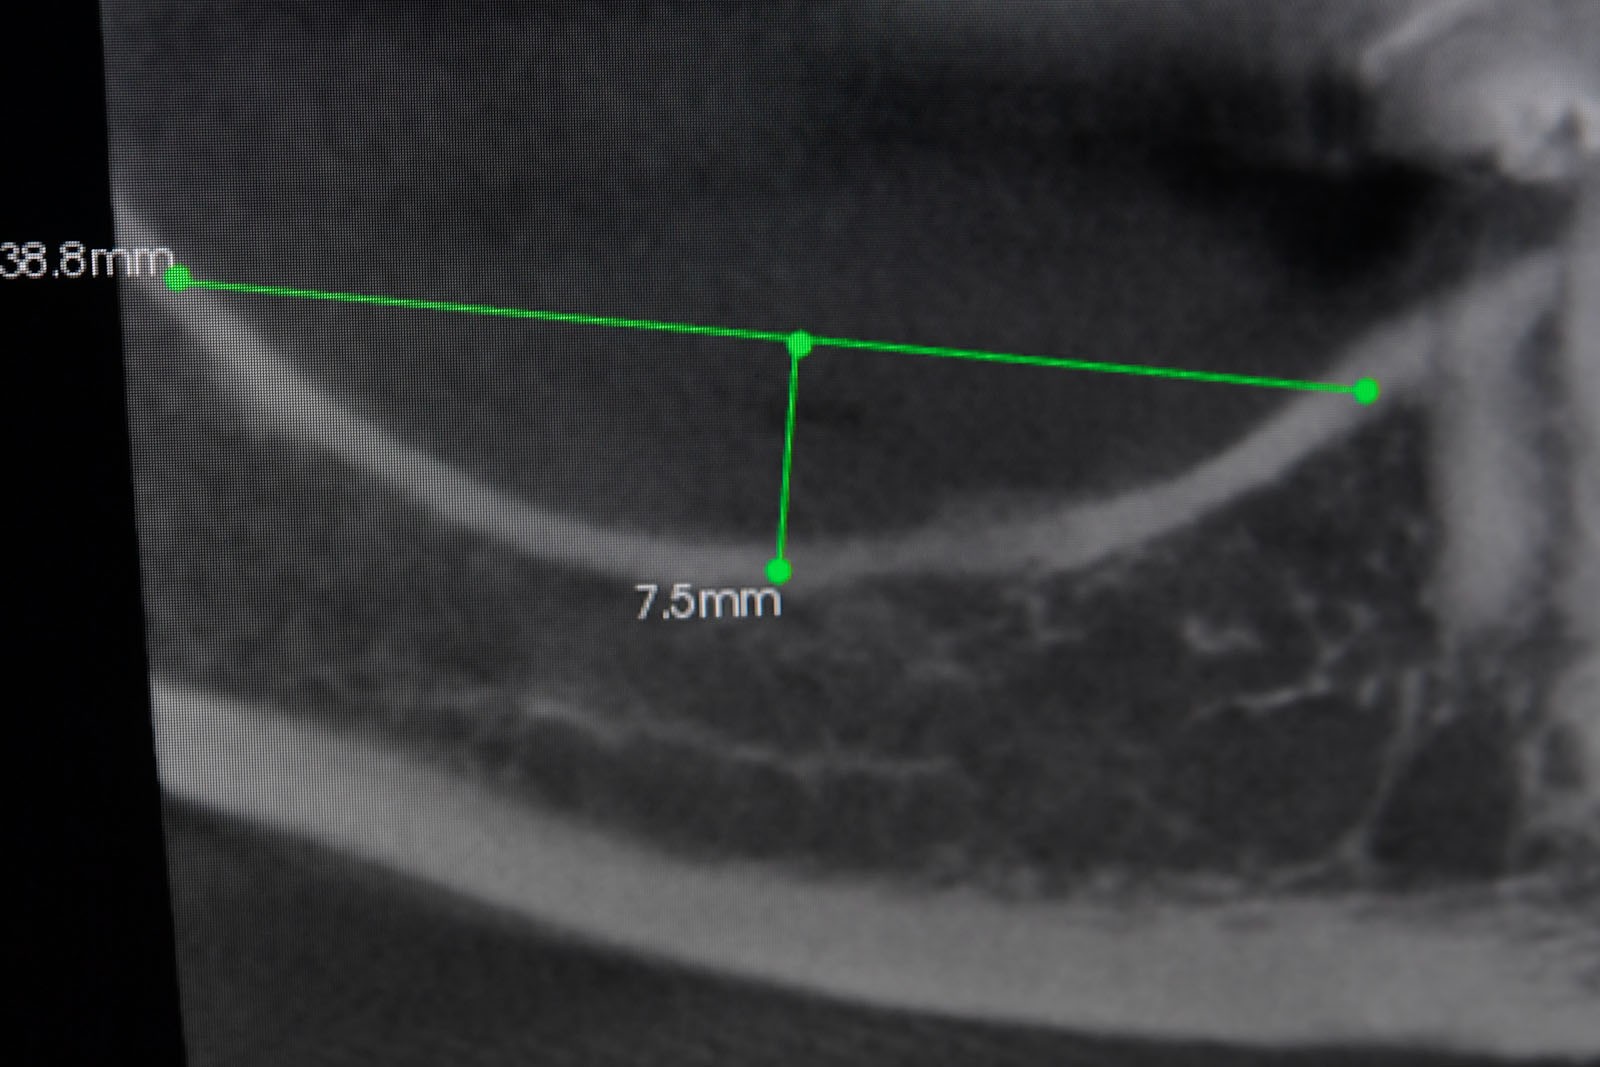

Przed podjęciem leczenia należy określić stopień zaniku kości szczęk oraz żuchwy. W tym celu przeprowadza się badanie kliniczne oraz odpowiednią diagnostykę obrazową pacjenta. Uwzględnia ona zdjęcie panoramiczne OPG jako podstawę dwuwymiarowego obrazowania podłoża kostnego oraz możliwe jest badanie tomograficzne CT lub bardziej precyzyjna tomografia stożkowa CBCT. Opcjonalnie wykorzystywana diagnostycznie tomografia pozwala na bardziej wnikliwą ocenę stopnia zaniku kości w trójwymiarowym, przestrzennym obrazie.

Zatoki szczękowe to symetrycznie umieszczone w kościach szczęk przestrzenie powietrzne, posiadające komunikację z jamą nosa. Średnio pojemność zatok wynosi 24 cm3, a ściany wyścielone są błoną śluzową (membrana Schneidera). Dno zatoki szczękowej stanowi wyrostek zębodołowy, w którym umieszczone są zęby, często zlokalizowane tuż pod cienką wyściółką zatoki. Statystycznie najwęższy obszar kostny w tej strefie zlokalizowany jest na wysokości zębodołów pierwszego i drugiego zęba trzonowego.

• Metoda otwarta – opisana w 1980 przez Jamesa i Boyna – polega na chirurgicznym dostępie do zatoki szczękowej poprzez jej boczną ścianę, następnie delikatnej preparacji, oddzieleniu wyściółki (błony Schneidera) bez jej perforacji, umieszczeniu pomiędzy nią a dnem zatoki materiału odbudowującego kość. Zabieg podniesienia dna zatoki szczękowej może przebiegać z jednoczesnym wszczepieniem implantów lub wszczepieniem ich w czasie odroczonym o 6–8 miesięcy. Warunkiem jednoczesnego wszczepienia implantów jest możliwość pierwotnie stabilnego ich umocowania w pozostałej własnej kości wyrostka zębodołowego. Najmniejsza jej ilość wg niektórych autorów to 1 mm.

• Metoda zamknięta – opisana w 1994 przez Summersa – bez szerokiego otwierania zatoki szczękowej, stosowana w sytuacjach wymagających niewielkiego zakresu rekonstrukcji na wysokość. W tej metodzie materiał regeneracyjny do odbudowy kości wprowadza się przez nawiercony kanał, komunikujący się z zatoką w pozycji zaplanowanej do wszczepienia implantu, lub tylko kondensuje się (zagęszcza, rozpycha i wydłuża) obszar kości dla uzyskania stosownej jej ilości i gęstości dla stabilnego umocowania implantu. Zabieg odbudowy kostnej wg Summersa wykonuje się przy użyciu specjalnego instrumentarium – zestawu osteotomów. Uzyskuje się dodatkowo 2–4 mm kości na wysokość